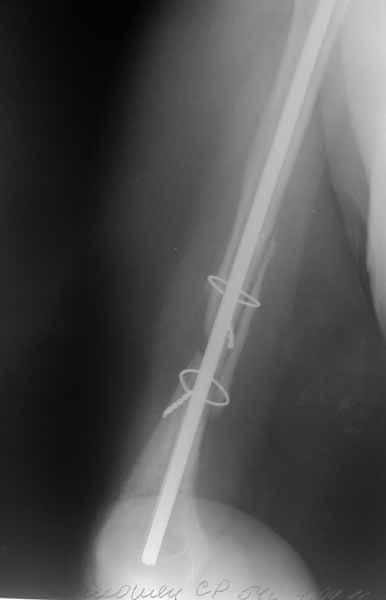

После БИОС